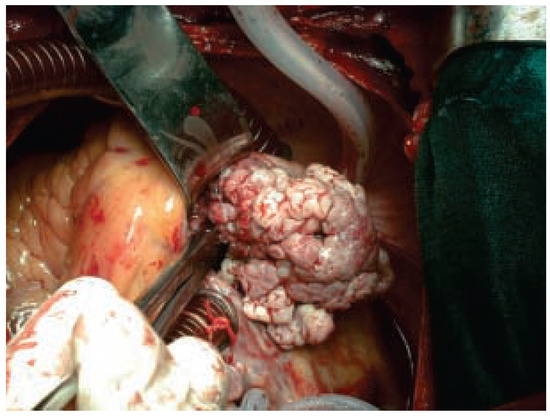

This article gives an overview on the practical management of device infections of chronically implanted pacemakers and implantable cardioverter- defibrillators. The main feature of such infections is the fact that the implanted materials have direct contact with the bloodstream, and therefore, may rapidly [...] Read more.

This article gives an overview on the practical management of device infections of chronically implanted pacemakers and implantable cardioverter- defibrillators. The main feature of such infections is the fact that the implanted materials have direct contact with the bloodstream, and therefore, may rapidly progress to systemic infection with serious septic complications. Apart from aggressive antibiotic treatment, in general, the infected material has to be explanted. Therefore, it is helpful to differentiate between the isolated pocket infection with the option of local surgical revision under preservation of the implanted leads and the systemic infection with the necessity of complete removal of all implanted materials using either the lead-extraction technique or open heart surgery. Full article